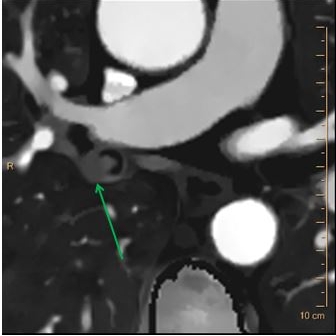

Case 2: Filling defects in left lower lobe pulmonary artery branches (red arrow).